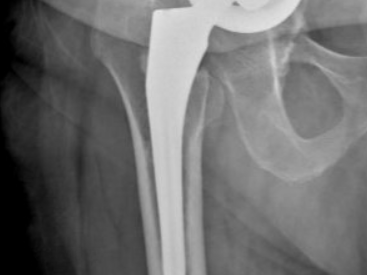

Le bilan radiologique (radiographies standards et scanner) recherche un liseré péri-prothétique correspondant à l’ostéolyse péri-prothétique voire même une migration des implants. Votre chirurgien étudiera l’ensemble de vos radiographies post-opératoire pour détecter l’apparition d’un liseré autour de la prothèse ou d’un déplacement des implants. Cependant, cet examen peut être normal.

Cas 1. Descellement de tige fémorale (liseré radiotransparent fémoral externe)